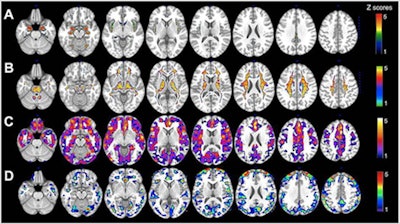

(A) MRI gray-matter volumes. (B) MRI white-matter volumes. (C) Pittsburgh compound B-PET beta-amyloid deposition. (D) FDG-PET glucose metabolism. Statistical parametric maps (SPMs) displaying brain regions showing Alzheimer's disease biomarker abnormalities in women versus men are represented on different color-coded scales after being thresholded to standardized z scores: 1 < z < 5, where z > 3 corresponds to p < 0.05 family-wise error corrected. All SPMs are displayed onto a standardized MR image. Image courtesy of Neurology, the medical journal of the American Academy of Neurology.Interestingly, despite the aforementioned differences, the researchers found no reduction in cognitive performance in women compared with men, including postmenopausal and perimenopausal women. The researchers suggested this finding supported the "notion that brain biomarkers are more sensitive than cognitive tests for the detection of Alzheimer's risk in asymptomatic individuals."

PET and MRI, respectively, revealed statistically significant differences (p < 0.05) between the genders in four categories. The women presented with the following:

- 30% more beta-amyloid plaques in women on average in the brain than men

- 22% less glucose metabolism, primarily in the superior frontal gyrus, medial frontal gyrus, and inferior parietal lobule

- 11% less gray matter volume (0.73 cm3) on average in women, compared with men (0.8 cm3)

- 11% less white matter volume (0.74 cm3) on average in women than men (0.82 cm3)